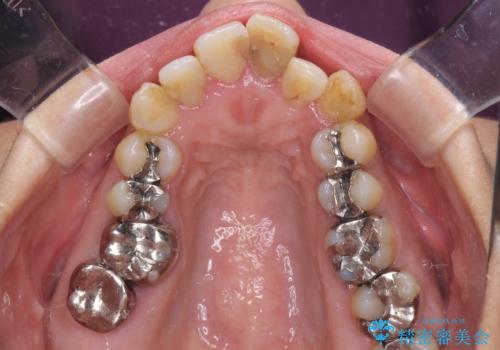

- 歯列全体が内側に倒れ込んでいることと、口元の突出感を気にして来院された患者様です。

上下ともに歯列が狭窄しており、前方に突出している状態でした。

歯が重なるような叢生も認められたため、上下左右の第一小臼歯4本を抜歯して、口元が引っ込むように治療を行うこととしました。

口元を引っ込めることができたため、口を閉じるときに力が入っていて皺のよっていた顎先も、スムーズに閉じられるようになったことで力がかからなくなりました。

変色して気になっていた前歯も、オールセラミッククラウンで自然な色合いにすることができました。